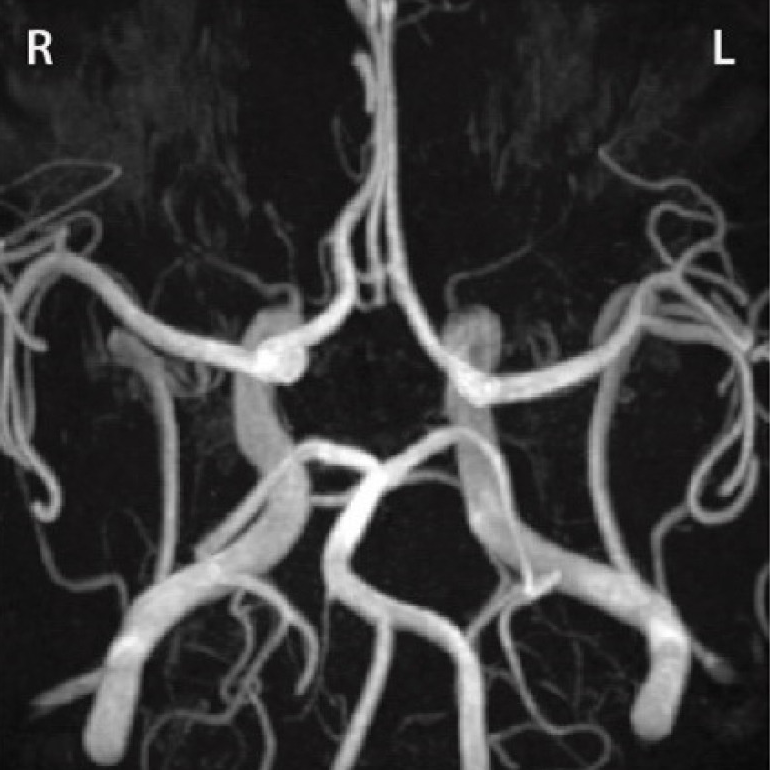

DQBM contributes to CROWN challenge study

A new publication in Medical Image Analysis presents results from the CROWN challenge, benchmarking automated techniques for Circle of Willis artery classification and quantification. The study involved contributions from the Menze Lab at DQBM.